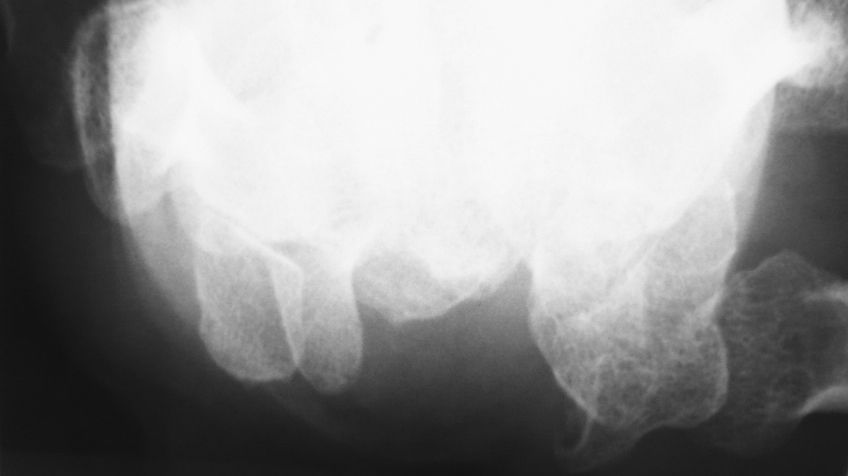

単純X線像では上記のように手根管内に小さな石灰化を認めました。発症機序と画像所見から石灰沈着性腱炎の一種だと診断しました。私は以前にも似たような症例を経験しています。

リリカとロキソニンを投与してしばらく経過観察していると発症後1ヶ月でかなり軽快しました。しかし、発症後2ヵ月で再度単純X線像を撮影したところ、石灰化はあまり変化ありませんでした。